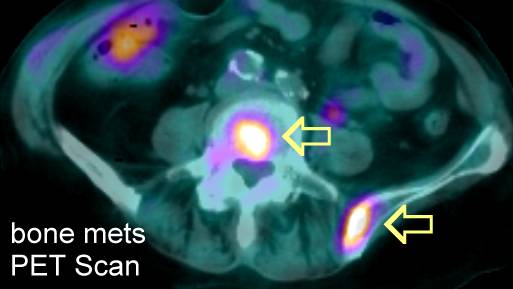

PET Scans of Bone Metastases

PET scans may show these lesions best (go here , here, here, here, here, here, here , here , here , here , here , here , here and here) even better than CT scans (go here , here, here and here) and better than MRI (here). PET scans also show the response to radiation (go here). PET is helpful for hard to see areas like the ribs or scapula. PET's may be best for

osteolytic lesions and bone scans best for blastic metastases (go

here). |